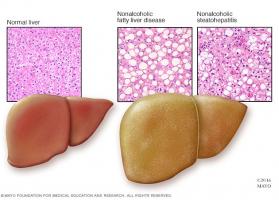

Actualité publiée le 03/11/2021De la STÉATOSE HÉPATIQUE à la stéatohépatite non alcoolique, quels mécanismes ?

Actualité publiée le 08/02/2021FOIE GRAS : Objectif exercice plutôt que perte de poids ?

Actualité publiée le 06/07/2020Du foie gras au cancer : Une immunothérapie pour prévenir le pire

Actualité publiée le 25/02/2020